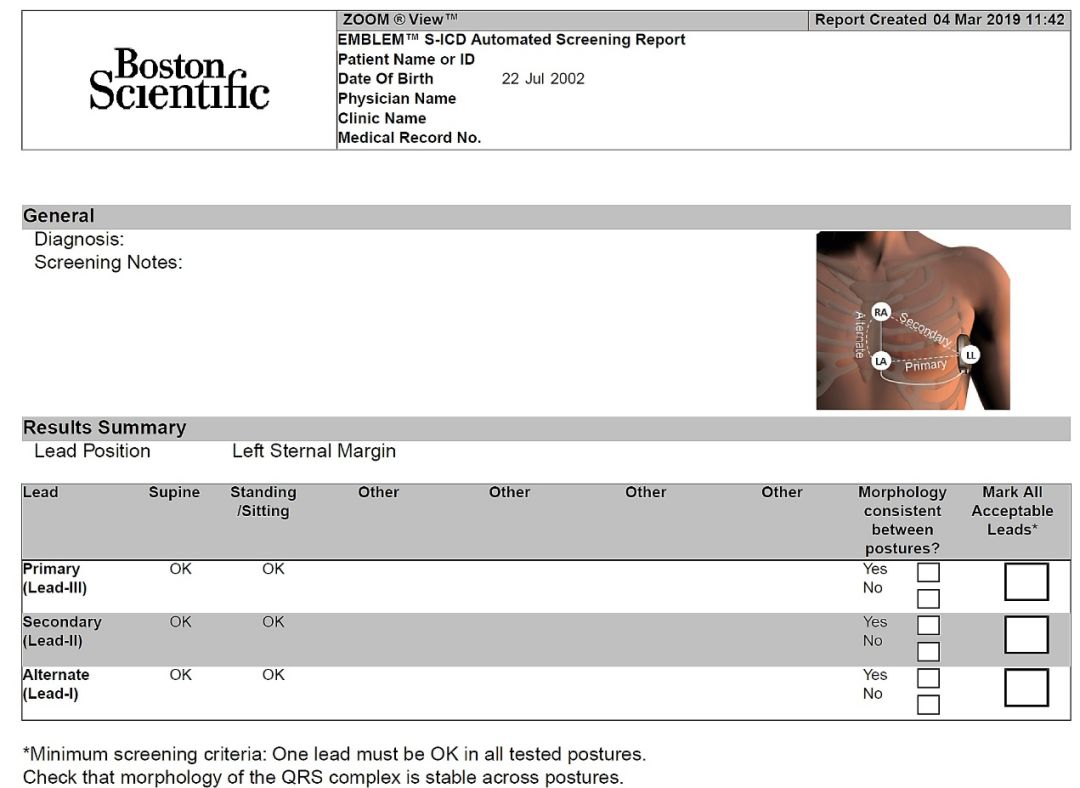

术前对患者进行了体表心电图筛查,左右两侧主要向量、次要向量和备选向量测量结果均符合筛查标准,综合以上,可以植入S-ICD。